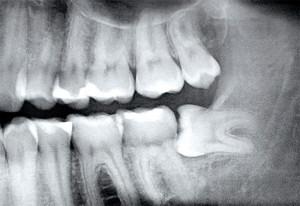

Если неприятных симптомов много, пациенту следует обратиться к стоматологу, чтобы узнать причину, по которой зуб мудрости не может нормально вырасти. Одной из самых распространенных является горизонтальный рост, когда моляр растет в неправильном направлении, лежит в десне и давит на весь зубной ряд.

- узкая челюсть – зубам мудрости не хватает места, так как они вырастают последними (см. также: );

- плотная костная ткань – «восьмерка» растет в ту сторону, где меньше сопротивление десны;